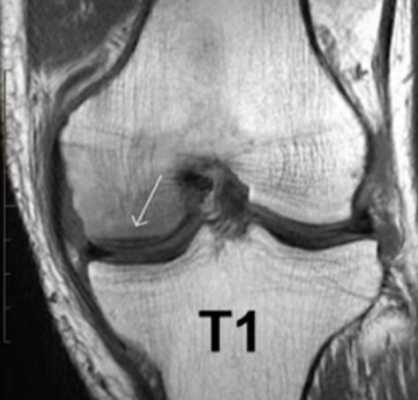

МР-скан коленного сустава в Т1 режиме (стрелкой указан костный отек)

При МРТ получают серии монохромных снимков анатомической области в аксиальной, сагиттальной и фронтальной плоскостях. При изучении изображений врач видит контуры различных элементов сочленения. Расшифровка МРТ-снимка коленного сустава подразумевает оценку сканов в сравнении с нормой. МР-томограммы называют срезами, поскольку изображения производят послойно, с шагом 1-2 мм. Врач последовательно изучает анатомическую зону на предмет соответствия всех структур норме. В процессе расшифровки фото обращают внимание на качество визуализации элементов, четкость контуров, присутствие зон измененного МР-сигнала (гипер- или гипоинтенсивного) в различных режимах сканирования (Т1 ВИ, Т2 ВИ, ДВИ, подавление жира).